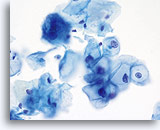

No diagnostic classification causes more debate than Atypical Squamous Cells (ASC). New terms rose from the revised classification of The Bethesda System (TBS) in 2001 and remain for TBS 2014. TBS indicates that the ASC category should be the diagnostic consideration when squamous abnormalities are present that are more marked than those attributable to reactive changes, but fall qualitatively or quantitatively short of the diagnostic criteria for a low grade or high grade squamous intraepithelial lesion. Furthermore, TBS stresses the importance of qualifying this diagnosis as “undetermined significance” (ASC-US) or “cannot exclude HSIL.” (ASC-H)

The proper classification of ASC challenges the cytotechnologist and pathologist and, writing any chapter describing the morphologic criteria of ASC is challenging, given the subjectivity of this interpretation. Since the adoption of TBS, laboratory professionals interpreting the conventional Pap smear may have used this category as a “catch all” for smears that are difficult to classify.

Artifacts inherent to the conventional Pap smear, such as air-dried or partially obscured cells, may result in an ASC diagnosis. The degree of apparent atypia in reactive cells may also be exaggerated by air-drying or smearing. These issues result in the artifacts that make it difficult for the cytotechnologist and pathologist to adequately visualize the nuclear detail of the cells in question, resulting in a less than definitive diagnosis.

The immediate wet fixation that is used in the ThinPrep process may allow the pathologist and cytotechnologist to move away from the ASC “catch all” and better differentiate between cellular changes due to reactive conditions, definitive squamous atypia, and dysplastic lesions. This is not to say that ASC interpretations are eliminated by the adoption of the ThinPrep Pap Test, but the laboratory staff has the opportunity to refine their morphologic criteria, eliminating certain “ASC” cases arising from poor preparation, and better identifying cases that may

harbor abnormality.

The ThinPrep Pap Test® minimizes the troublesome artifacts inherent in smear and spray fixation. This allows for

the nucleus to be adequately visualized facilitating a more definitive diagnosis. The epithelial cells that are generally incorporated in the ASC category are the mature squamous and squamous metaplastic cells exhibiting changes that are minimal and fall short of a diagnosis of LSIL or HSIL. The nuclei are slightly enlarged and this enlargement is compared to the normal entity of the same cell type. The nuclei may show slight nuclear membrane irregularities but are more often smooth. When dealing with the metaplastic component, one needs to make sure that the irregularities aren’t due to a vacuole(s) pushing the nucleus into the aberrant shape. The chromatin pattern is finely granular and evenly distributed. Chromocenters or nucleoli are generally inconspicuous or absent unless a reactive process is occurring in conjunction with the atypia at which point the differential diagnosis of reactive needs to be considered depending upon the presence or lack of the other criteria.

With either conventional or ThinPrep® slides, an ASC interpretation may arise from any of several different cellular changes, including but not limited to, squamous atypia, atypical squamous metaplasia, and atypical parakeratosis. The criteria for ASC on the ThinPrep Pap Test are as follows:

| REACTIVE | ASC-US | LSIL | |

| Nucleus | Enlarged 1.5-2 times,flat | Enlarged 2 -3 times, flat to minimal depth of focus | Enlarged 3-4 times,Slight depth of focus |

| Nuclear Membrane | Smooth | Smooth to slightly irregular | Smooth to slightly irregular |

| Chromatin | Finely granular, evenly distributed | Finely granular, evenly distributed | Slightly more granular, evenly distributed |

| Nucleoli/Chromocenters | Small to conspicuous, sometimes multiple | Inconspicuous or absent | Absent |

| Cytoplasmic Features | Peri-nuclear halos present | Questionable cavitations | Diagnostic HPV cavitations |

| Bichromasia | Can be present | Not present | Not present |

The images that follow are ThinPrep® Pap Test specimens that reasonably could be interpreted as reactive changes,

ASC-US, and LSIL.

As previously mentioned, ASC will not be eliminated by the adoption of the ThinPrep® Pap Test. In fact, the better cellular preservation that is afforded by liquid fixation can lead to over interpretation of nuclear size and chromatin as ASC if one is not familiar with the consequences of liquid fixation as discussed in the introductory material regarding “microscopic evaluation of ThinPrep slides”. There are circumstances where laboratory staff may transiently experience an increase in their use of ASC classification immediately after adoption of the ThinPrep Pap Test, then, after gaining experience, see that rate drop below that which was experienced with the conventional Pap.

ASC, as long as it remains a category in TBS, will be used by pathologists because of inherent subjectivity of human diagnosis, and variable interpretation of criteria. Also important is the biologic nature of Human Papilloma Virus (HPV) that causes morphologic perturbations in cells that are less than LSIL. The morphologic changes caused by HPV are discussed in greater detail in the section covering Low Grade Squamous Intraepithelial Lesions. The role of this virus in the causation of ASC has created the opportunity to determine the relative risk of ASC changes by the determination of high- vs. low-risk types of virus through ancillary testing of the material in the ThinPrep Pap Test vial.